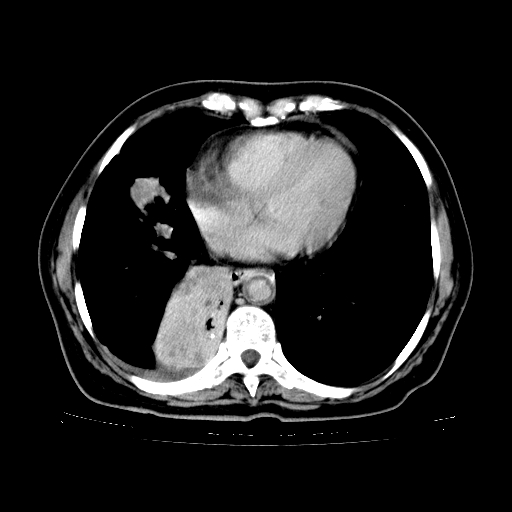

女,70岁,咳嗽、咳痰一个月,低热一周。

1.左上肺结核,部分纤维化。右肺中下叶部分肺不张,内见液化、坏死及点状钙化,右中下叶支气管壁增厚、管腔狭窄,见多个点状钙化,结合临床考虑支气管内膜结核,建议痰检查抗酸杆菌并参考血沉。两肺多个小圆点状高密度灶,境界模糊,多考虑结核肺内播散。但本人年龄较大首先应支气管镜检以除外右肺癌。

2.胸主动脉夹层。

1、右肺占位,考虑周围型ca 。

2、右下肺软组织密度肿块影,考虑肺隔离征。

3、两肺肺结核(右肺下叶背段及左肺)。

4、主动脉夹层。

5、右侧少量胸腔积液。